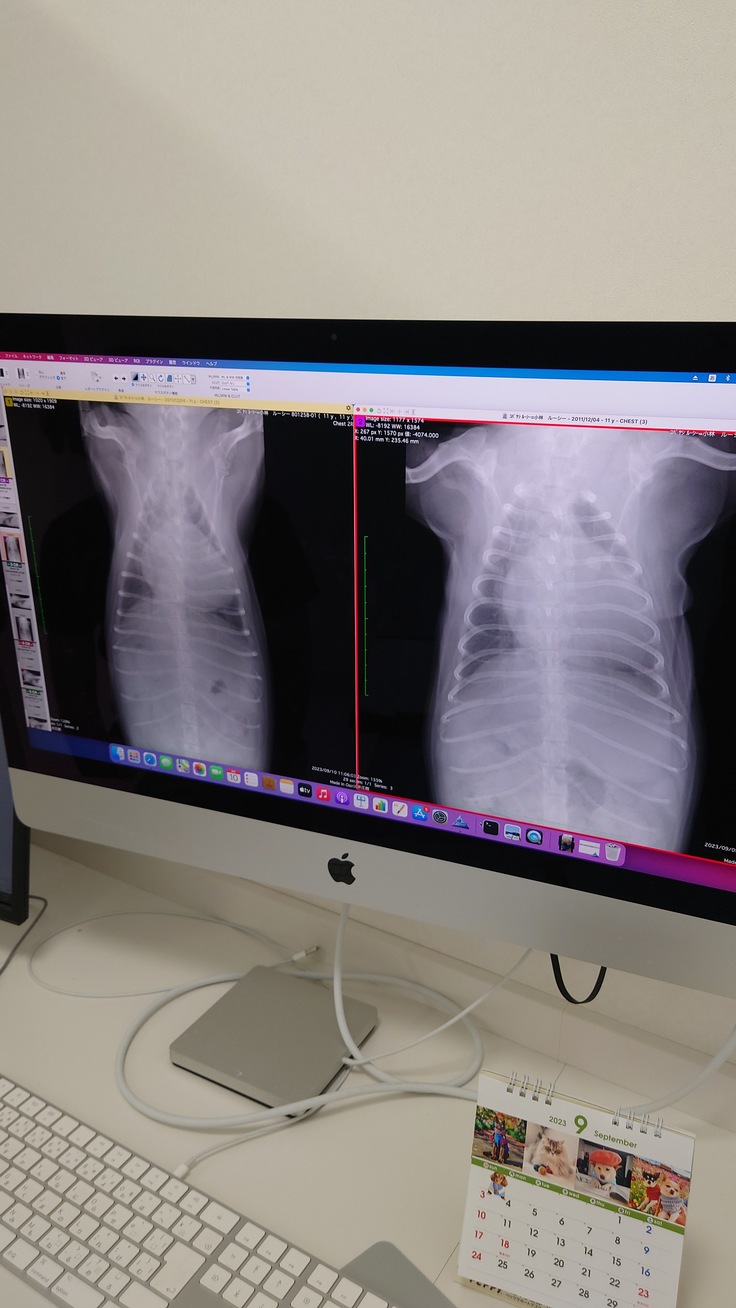

右が入院前の肺、左が今日の朝の段階での肺の状態です。

白い部分が水が入っている部分になりますが、

明らかに今朝のほうが黒い部分が多くて、

肺に水が溜まっていないのがわかります。